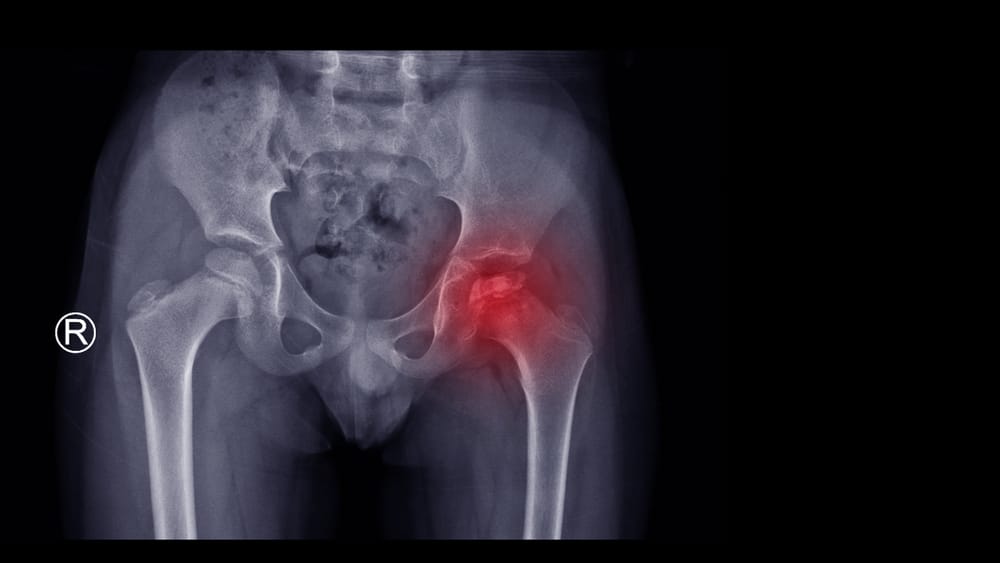

Osteoporosis is a condition in which bones become weak and brittle, making them more susceptible to fractures even with minor stress or injury. Often referred to as a “silent disease,” osteoporosis may not exhibit noticeable symptoms until a fracture occurs, which is why prevention, early detection, and proper treatment are crucial. Strong bones support mobility, independence, and overall quality of life, especially as we age.

How Osteoporosis Is Diagnosed

Accurate diagnosis is essential for effective treatment. Common diagnostic tools include:

- Bone Density Scans (DEXA): Measures bone mineral density to detect early bone loss.